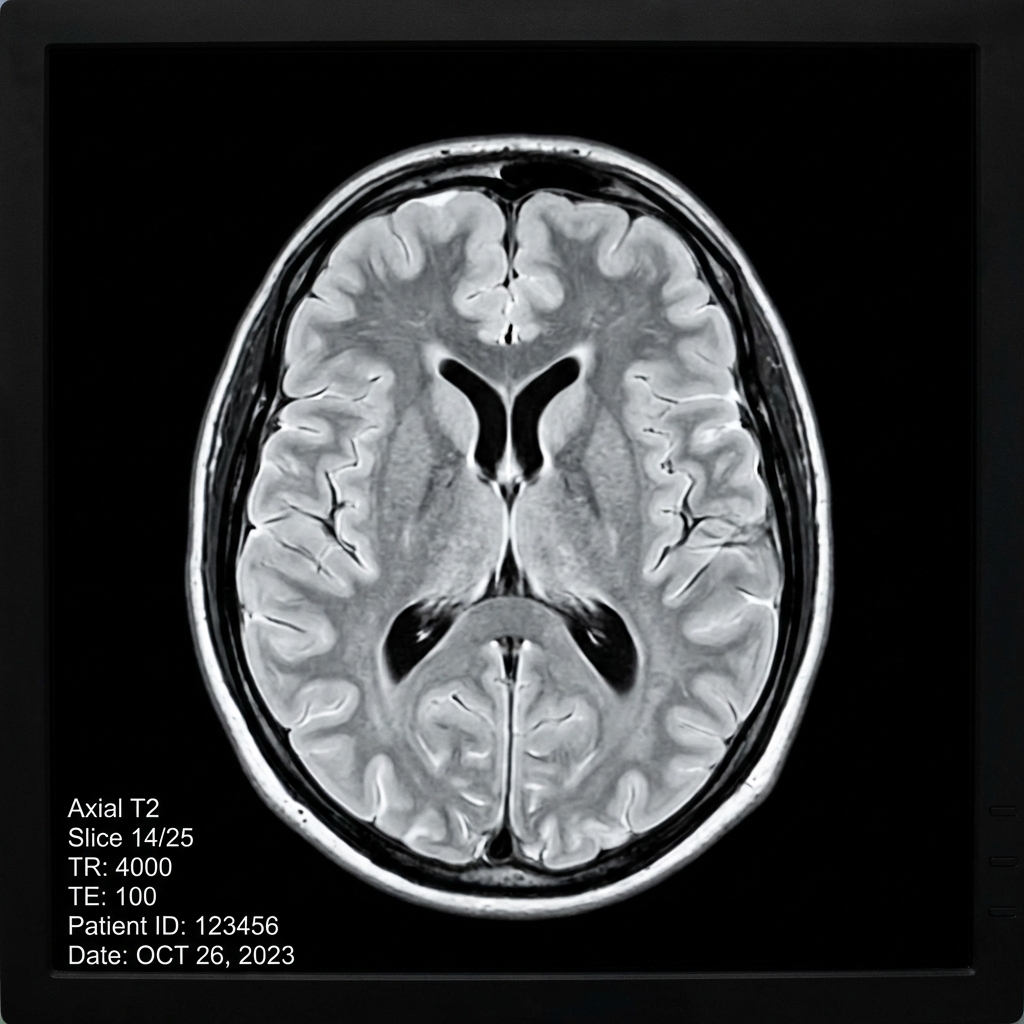

Ornek goruntu:

Beyin MR